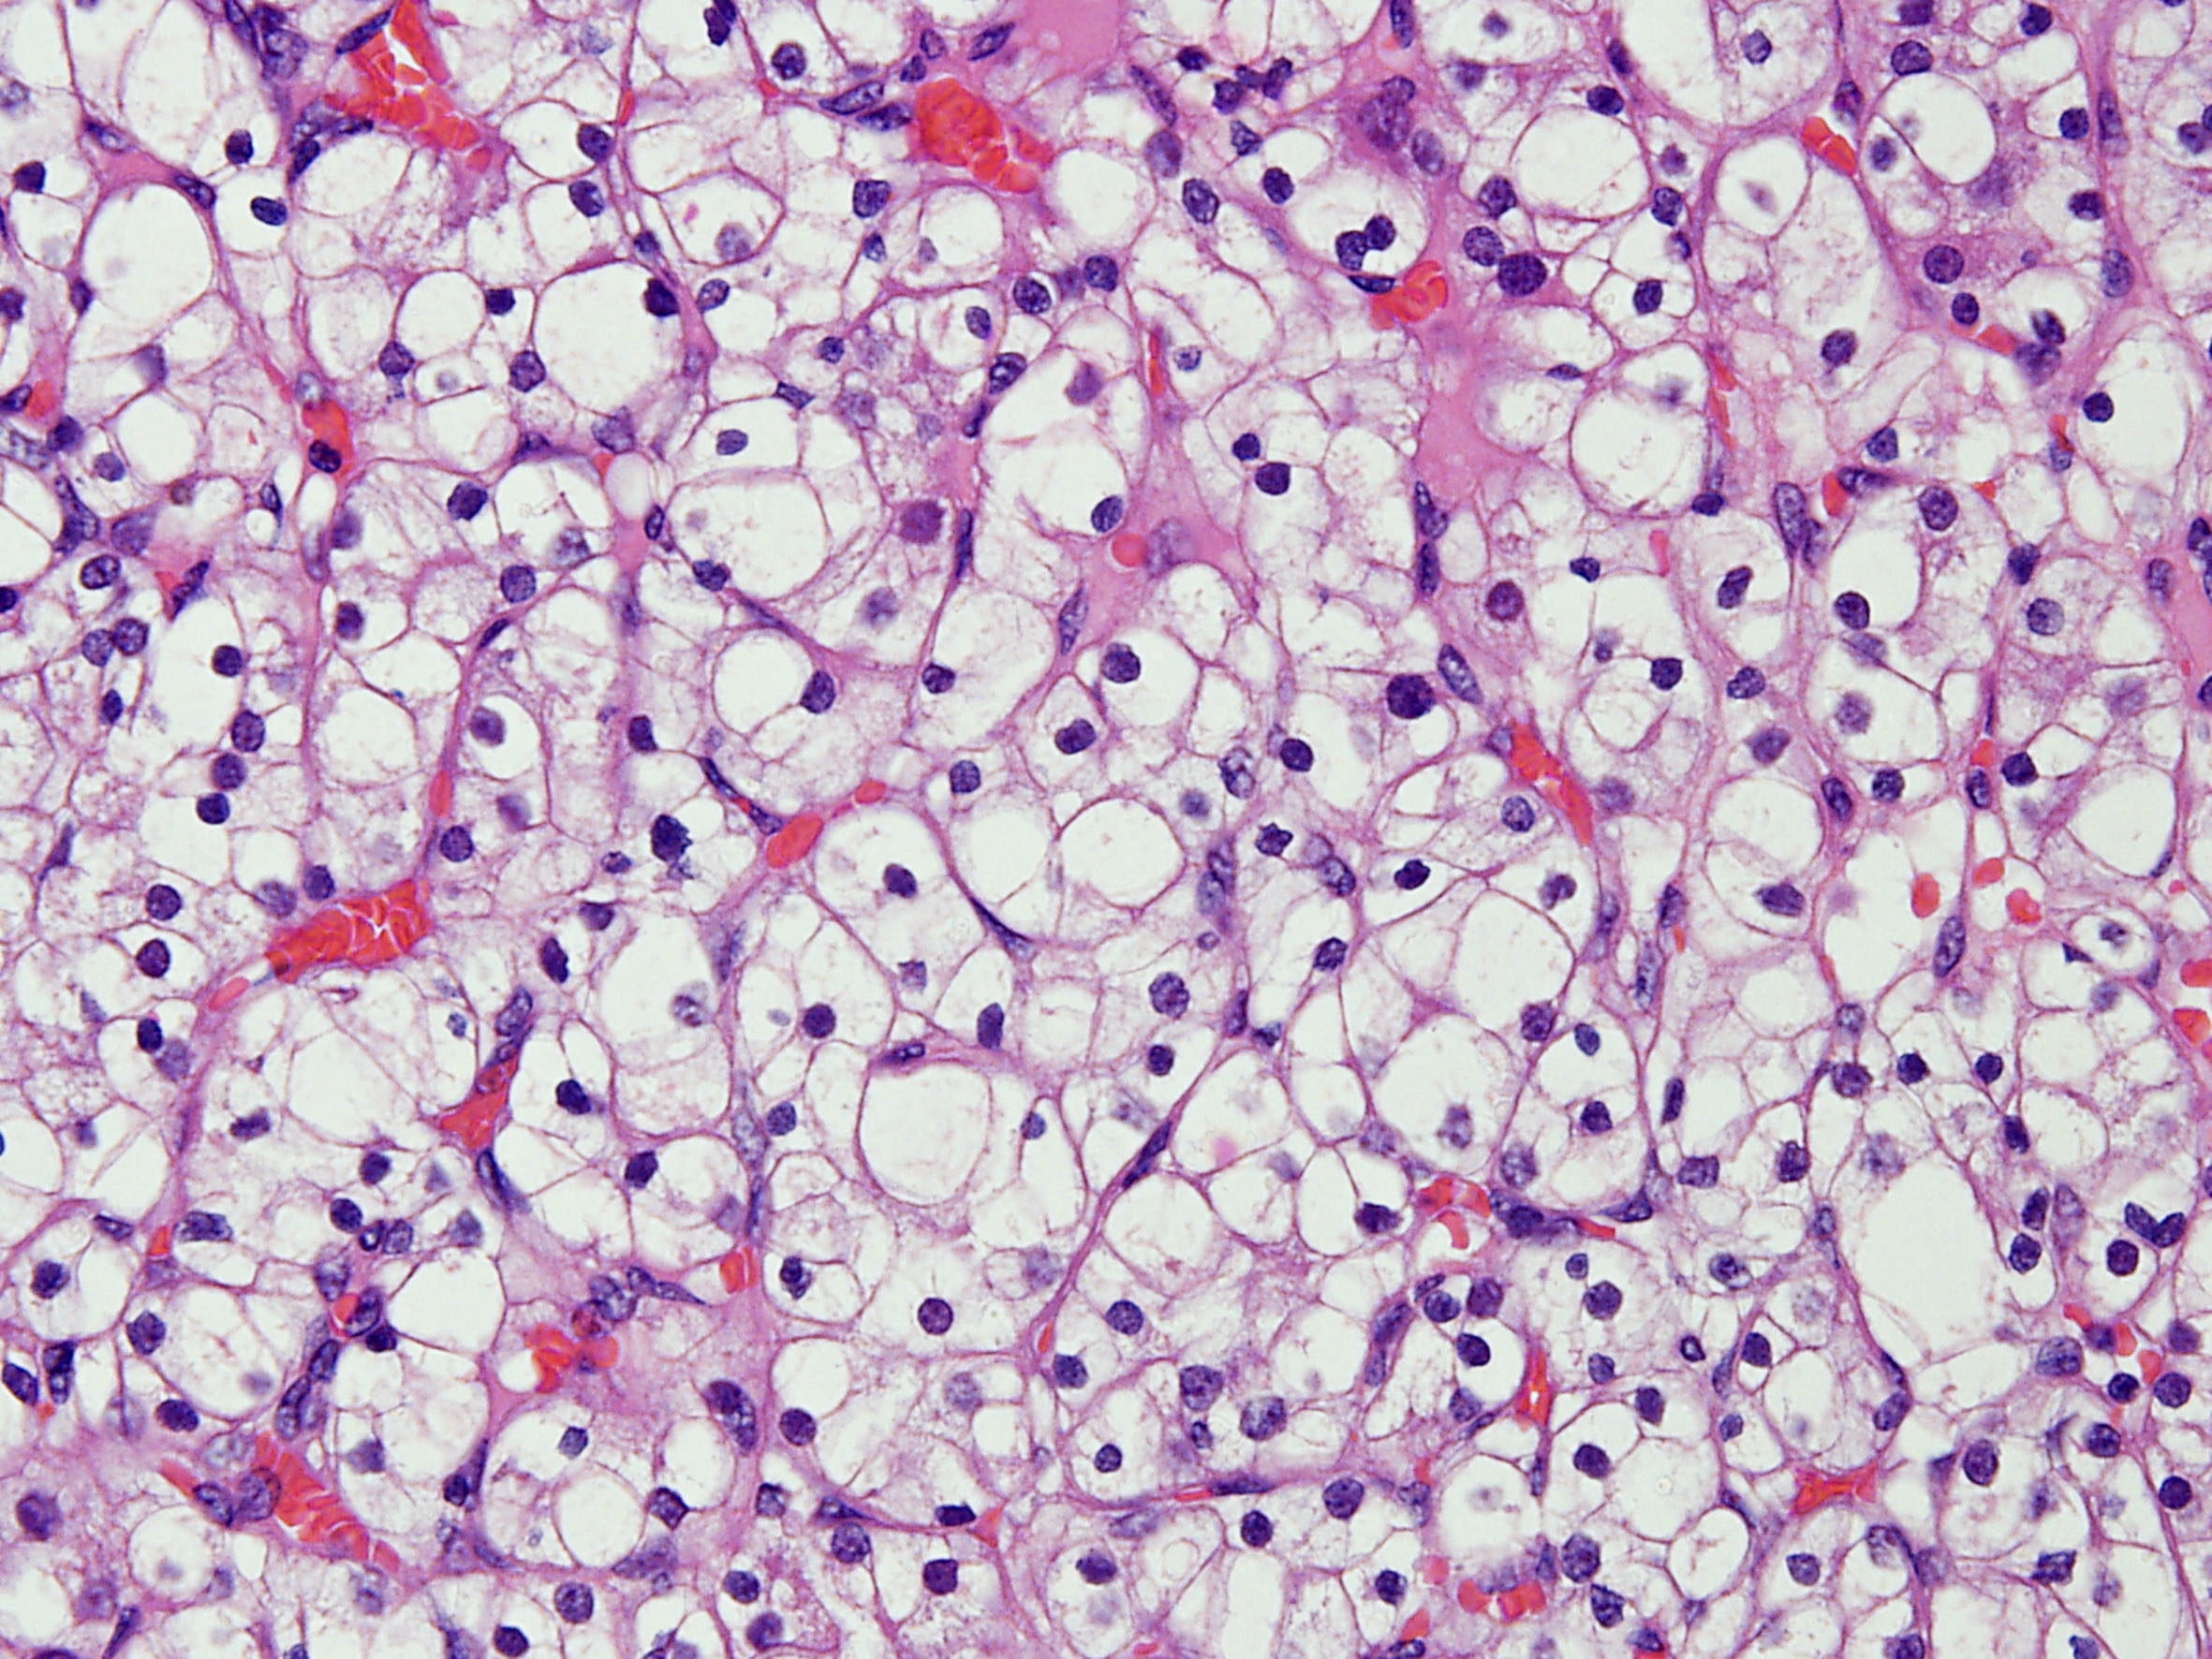

Classification of renal tumors

Case ID: 184